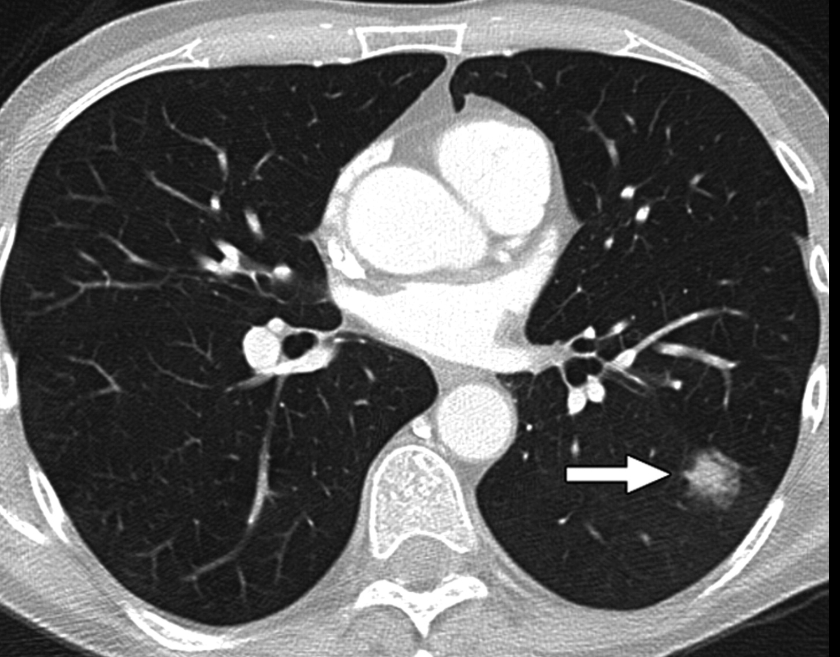

흉부ct로 볼수있는 질환 폐질환뿐 아니라 심장과 혈관, 흉막, 림프절, 뼈 구조까지 한 번에 보여줍니다. 폐렴, 결핵, 폐기종, 기관지확장증, 간질성 폐질환 같은 호흡기 질환은 기본이고, 폐에 생긴 작은 결절이나 혹도 세밀하게 확인할 수 있습니다. 폐암이나 전이암처럼 초기에 증상이 거의 없는 병은 CT로 발견되는 경우가 많아요.

혈관 관련 질환으로는 폐색전증(혈전이 폐혈관을 막는 병)이나 대동맥 박리(혈관 벽이 찢어지는 상태), 흉부 대동맥류(혈관이 부풀어 터질 위험이 있는 질환) 등이 있습니다. 조영제를 주입하면 혈관 내부 흐름까지 볼 수 있죠.

흉부CT는 병이 있는지 없는지를 넘어서, 병의 진행 정도와 주변 장기 침범 여부까지 보여줍니다. 예를 들어 폐암의 경우, 5mm 미만의 아주 작은 결절까지 찾아내고, 종양이 혈관이나 기관지에 닿았는지도 확인합니다. 초기에 잡아내면 완치율이 크게 높아지죠.

또한 폐렴이 감염인지, 결핵성인지, 종양에 의한 것인지도 구분할 수 있습니다. 엑스레이에서는 그냥 ‘흐린 그림자’로만 보이던 것도, CT에서는 염증의 경계와 내부 구조까지 뚜렷하게 드러납니다.